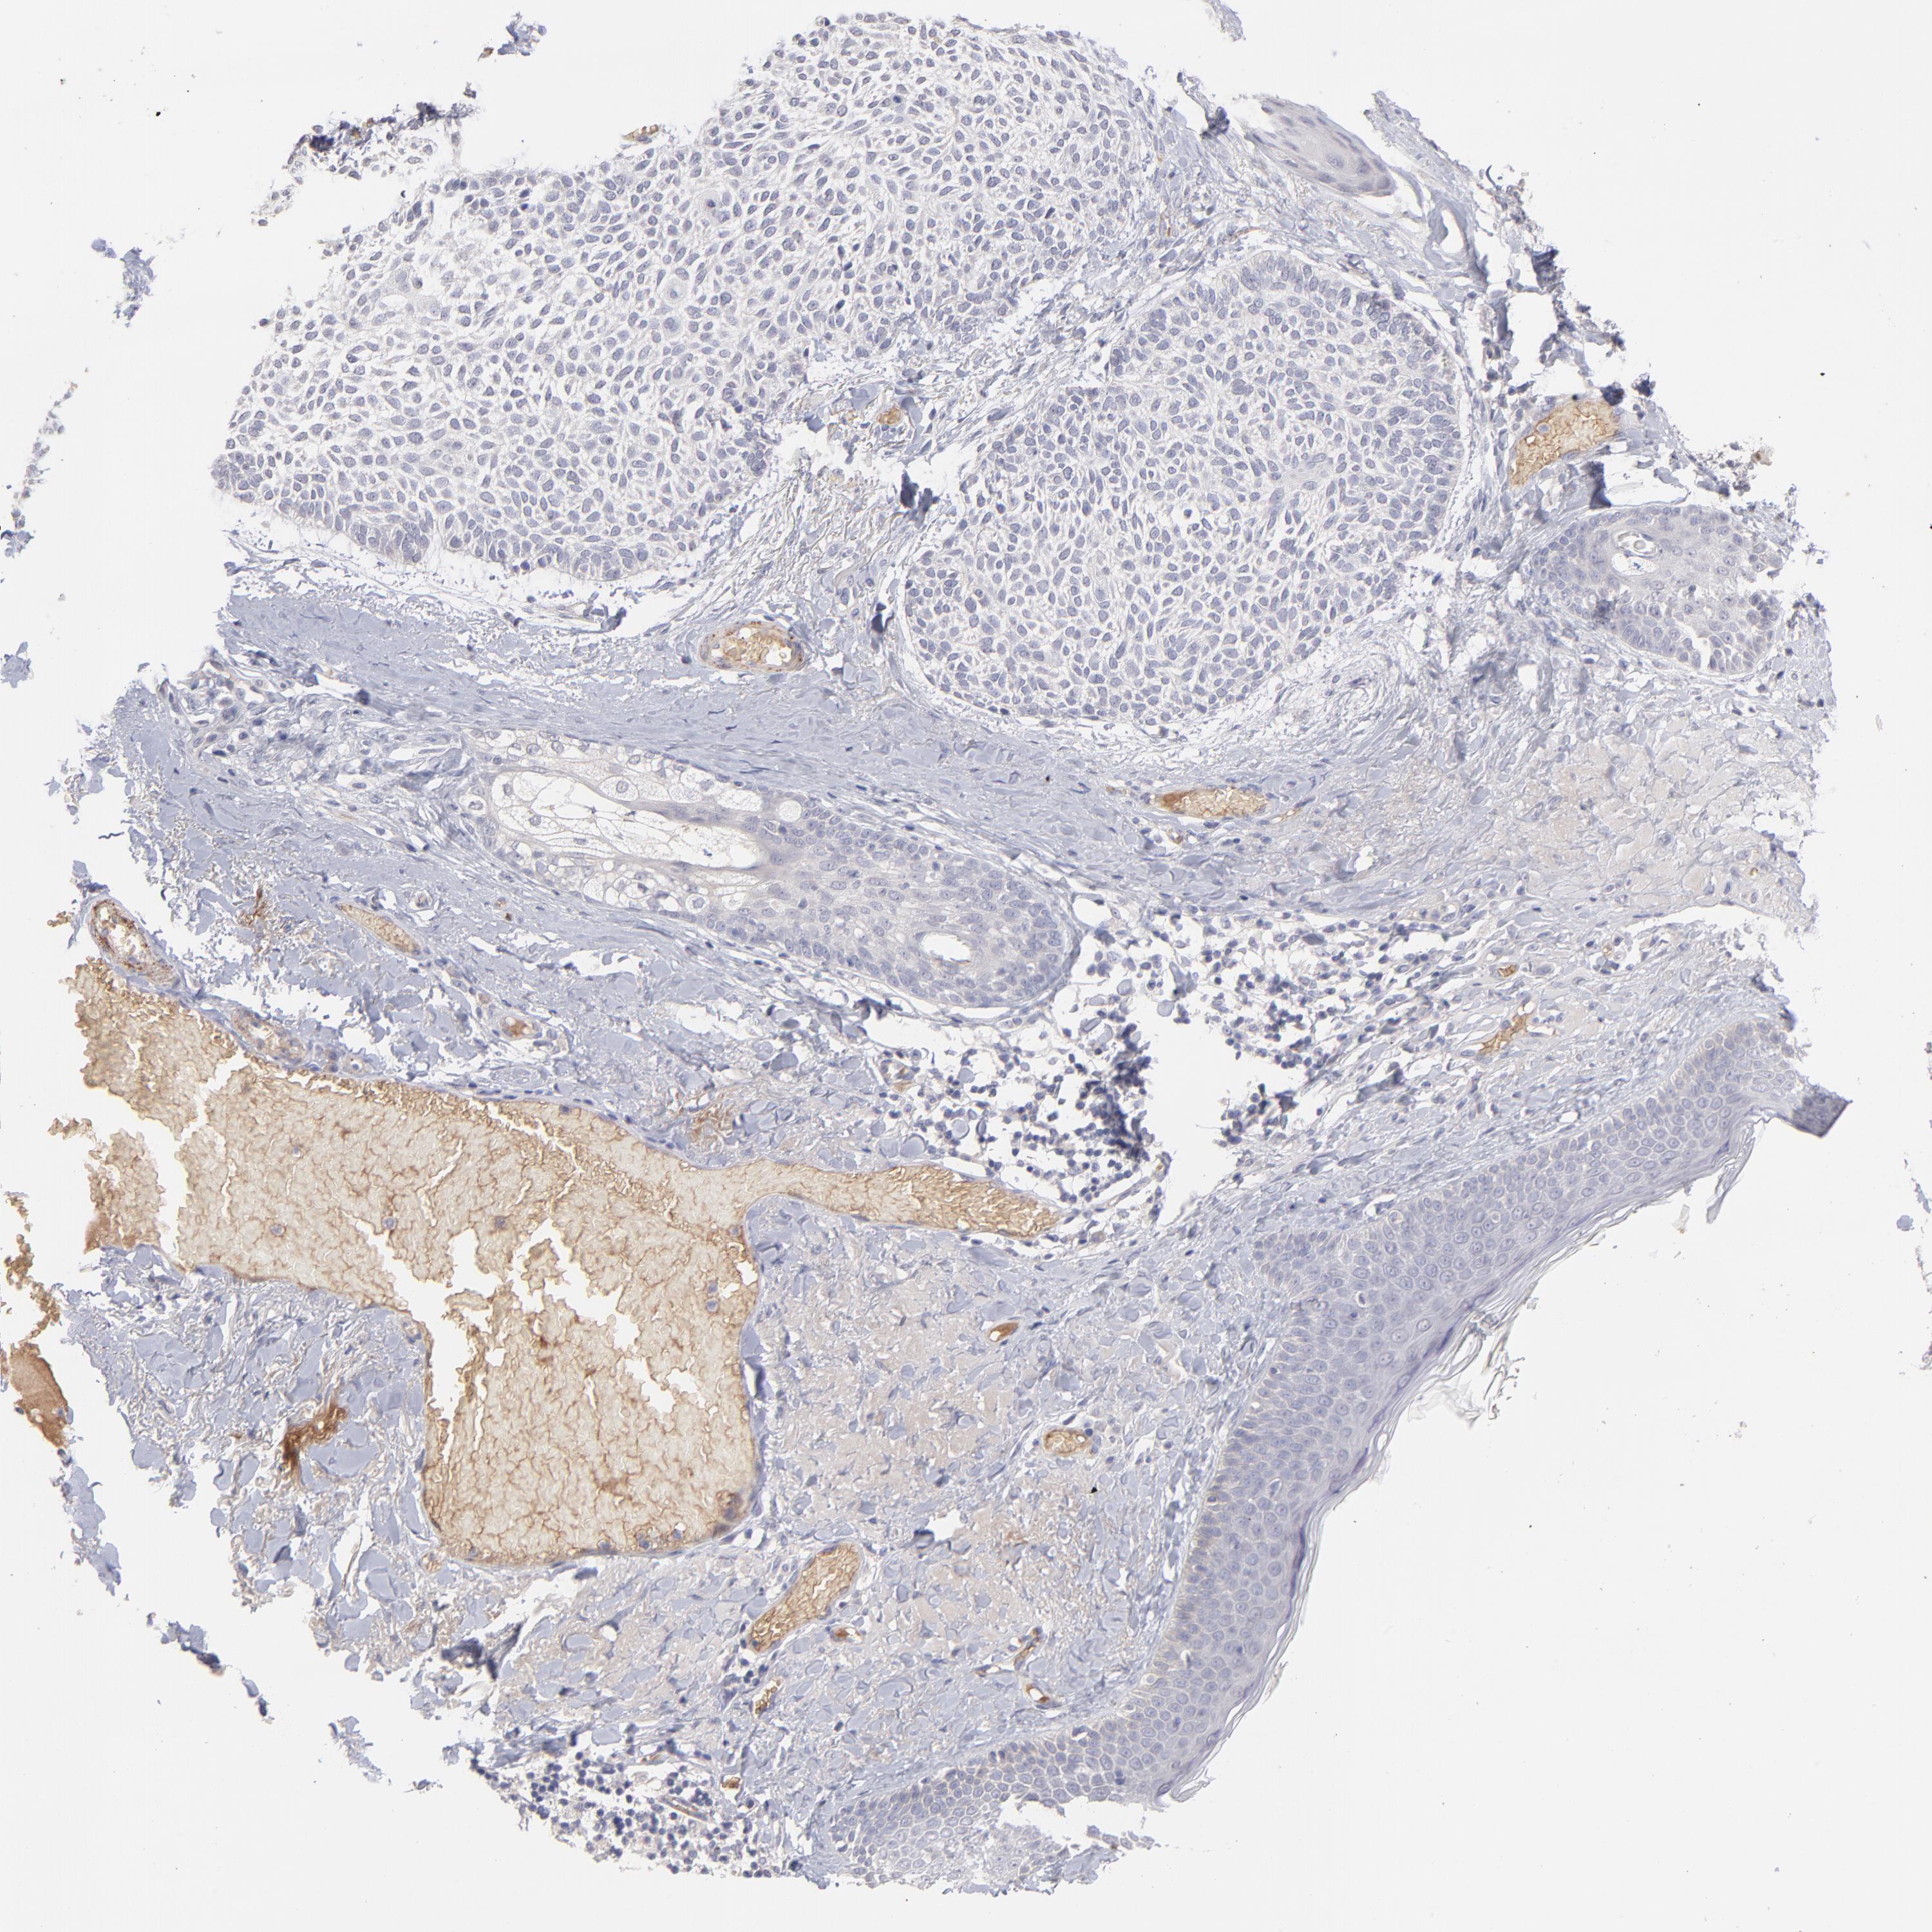

Basal cell and squamous cell cancer

SKIN CANCER - Protein expressioni

A mouse-over function shows sample information and annotation data. Click on an image to view it in a full screen mode. Samples can be filtered based on level of antibody staining by selecting one or several of the following categories: high, medium, low and not detected. The assay and annotation is described here.

Antibody stainingi

Antibody staining in the annotated cell types in the current human tissue is reported as not detected, low, medium, or high, based on conventional immunohistochemistry profiling in selected tissues. This score is based on the combination of the staining intensity and fraction of stained cells.

Each image is clickable and will lead to virtual microscopy that enables deeper exploration of all samples and also displays staining intensity scores, fraction scores and subcellular localization as well as patient and tissue information for each sample.

Antibody HPA003827

Antibody HPA052139

Staining

High

Medium

Low

Not detected

Intensity

Strong

Moderate

Weak

Negative

Quantity

>75%

75%-25%

<25%

None

Location

Nuclear

Cytoplasmic/membranous

Cytoplasmic/membranous,nuclear

Squamous cell carcinoma, NOS

Basal cell carcinoma